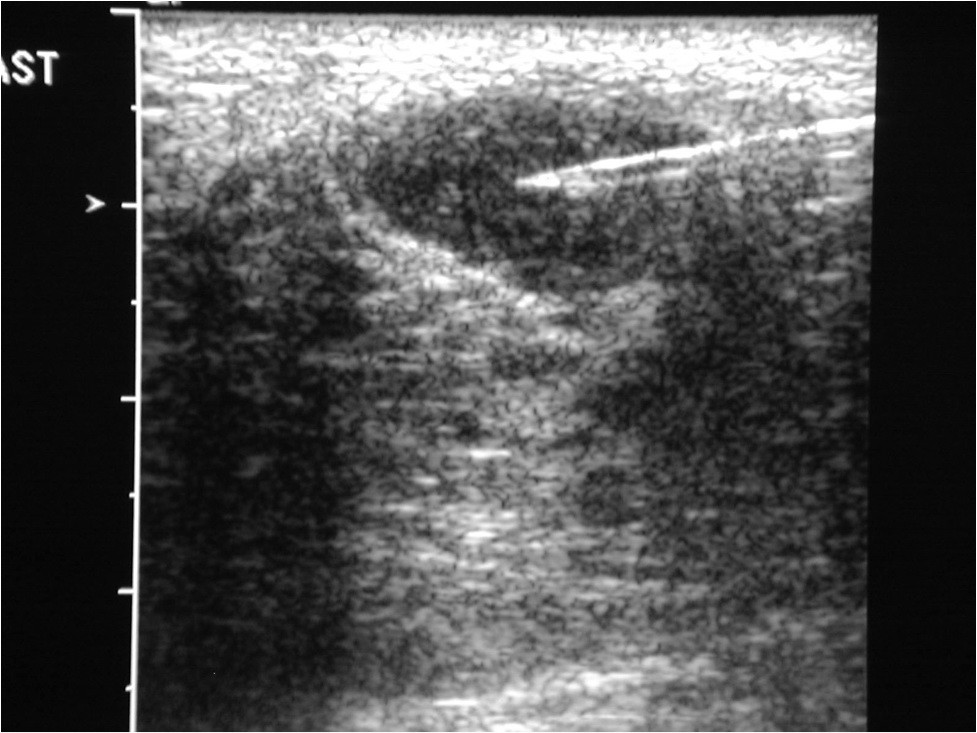

W jej ramach istnieje możliwość, USG piersi, BAC czyli cienkoigłowej biopsji aspiracyjnej a także diagnostyczne i lecznicze wycięcie zmian przed- i nowotworowych skóry.